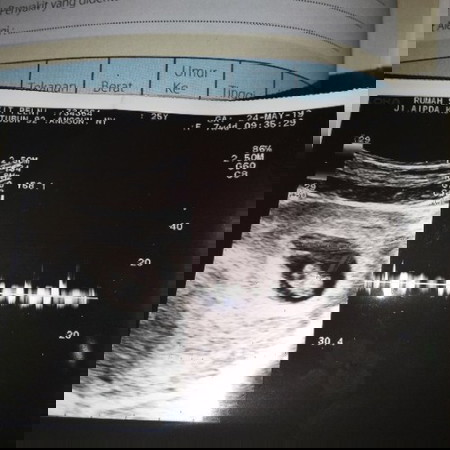

bun mau tanya ini kan hasil usg 7 mnggu. dokter blg td udah ada detak jantungnya.. cm aku kya salah denger udah ada kepala apa belom gitu saking seneng denger jantungnya ga smpe na ya2 detail. kalo begini udah kebentuk blm si bun?? hehe maklum anak pertama

Iya itu bakal janin.. Bentuk kepala smpe kaki blm terbentuk jelas semua..

Belooom mom..